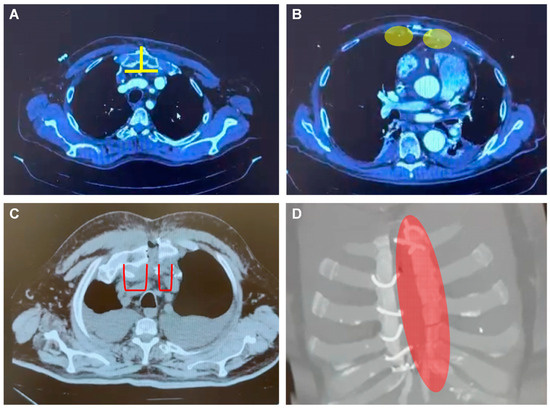

- Intihar, U.; Zeleznik, J.; Brajlih, T.; Drstvensek, I.; Hudak, R.; Antonic, M. Sternal Reconstruction Using 3D-Printed Titanium Custom-Made Prosthesis for Sternal Dehiscence After Cardiac Surgery. Heart Surg. Forum 2023, 26, E160–E163. [Google Scholar] [CrossRef] [PubMed]

- Kamel, M.K.; Cheng, A.; Vaughan, B.; Stiles, B.; Altorki, N.; Spector, J.A.; Port, J.L. Sternal Reconstruction Using Customized 3D-Printed Titanium Implants. Ann. Thorac. Surg. 2020, 109, e411–e414. [Google Scholar] [CrossRef]

- Wang, H.; Liu, Z.; Chen, C.; Liu, M.; Xiao, Y.; Zhang, J.; Yu, G.; Jiang, G. Sternal Resection and Reconstruction With a Novel Modularized Prosthesis. Ann. Thorac. Surg. 2020, 110, 1412–1416. [Google Scholar] [CrossRef]